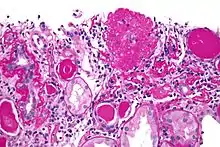

| Light micrograph of focal segmental glomerulosclerosis, hilar variant. Kidney biopsy. PAS stain. | |

On histology, FSGS manifests as scarring (sclerosis) to segments of glomeruli; moreover, only a portion of glomeruli are affected.[7][20][21] The focal and segmental nature of disease seen on histology help to distinguish FSGS from other types of glomerular sclerosis.[21]

Diagnosis of FSGS is made by renal biopsy that includes at least fifteen serial cuts with at least eight glomeruli.[31][32] Histologic features include sclerosis (scarring) of a portion (average: 15%) of the glomerular space, with only a portion of glomeruli manifesting any sclerosis.[32]